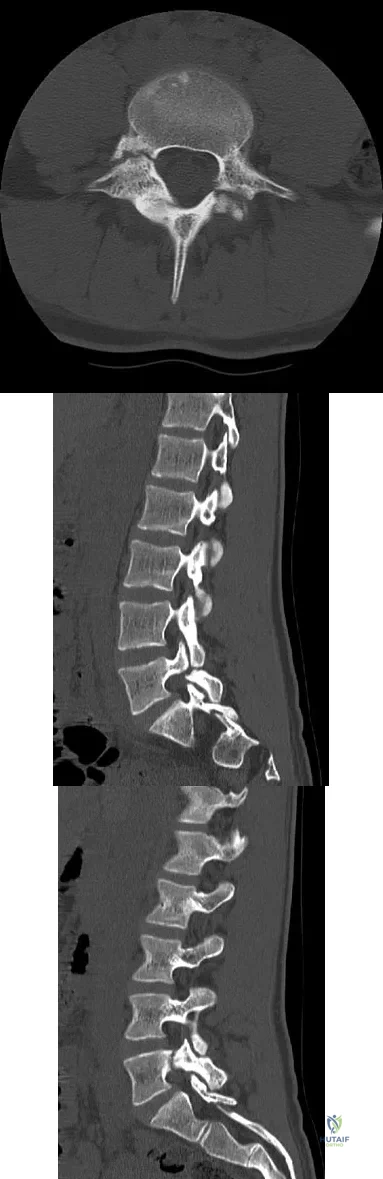

An 18-year-old collegiate basketball player has had a 3-month history of activity-related back pain. She describes isolated low back pain without radiation that increases with training and playing basketball. Her pain resolves with rest. Physical therapy for 6 weeks has failed to provide relief. An axial CT scan is shown in Figure 17a, and Figures 17b and 17c show sagittal CT reconstructions through the right and left lumbar facets, respectively. Further management should consist of which of the following?

Explanation